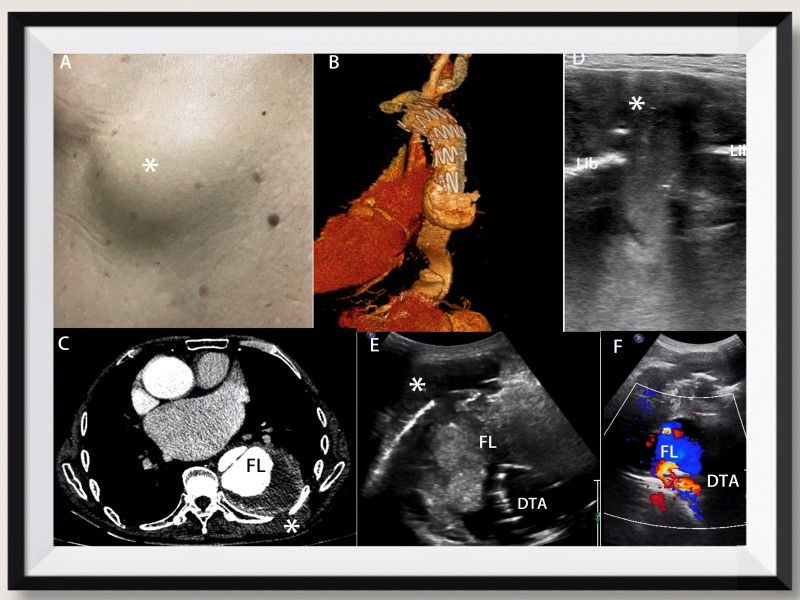

近期,医学影像学院教师马宁帅(第一作者和通讯作者)的研究论文“A rare case of a dorsal mass caused by descending thoracic aortic dissection”在国际顶级学术期刊(中科院分区医学1区)《European Heart Journal》上成功发表(影响因子35.855)。

文章以一例成因少见的背部包块的病例为基础,详述了B型胸主动脉夹层支架植入术后比较“奇怪”的复发方式以及诊疗过程。作者着重突出了超声和CT相结合在本病中的诊断价值,此类病例通过超声可以实时动态观察到低回声的液体物质在假腔和皮下包块之间来回流动,对于直观形象的理解降主动脉血进入皮下软组织内的病理生理过程起到了良好的辅助作用,该研究成果对于胸降主动脉瘤的诊疗具有重要的借鉴和指导意义。